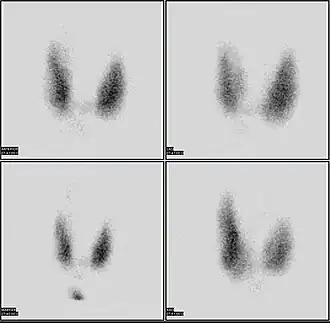

A nuclear medicine parathyroid scan demonstrates a parathyroid adenoma adjacent to the left inferior pole of the thyroid gland. The above study was performed with Technetium-Sestamibi (1st column) and iodine-123 (2nd column) simultaneous imaging and the subtraction technique (3rd column).

A nuclear medicine parathyroid scan demonstrates a parathyroid adenoma adjacent to the left inferior pole of the thyroid gland. The above study was performed with Technetium-Sestamibi (1st column) and iodine-123 (2nd column) simultaneous imaging and the subtraction technique (3rd column). -